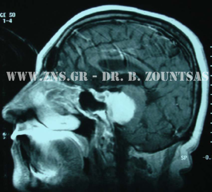

Ολική εξαίρεση μηνιγγιώματος πτέρυγας σφηνοειδούς

Ολική εξαίρεση μηνιγγιώματος λιθοειδούς αποκλίμματος